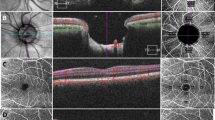

Table 2 summarizes the means, ICCs, and CVs for peripapillary OCTA parameters obtained at the initial visit. For VD, the CV was 2.94–4.08% and the ICC was 0.918–0.929, indicating good repeatability for all areas. For PD, the CV was 3.17–4.22% and the ICC was 0.840–0.934, indicating good repeatability. In the Bland–Altman plots, the differences were close to 0 for all parameters (Fig. 1).

Table 3 summarizes the means, ICCs, and CVs for peripapillary OCTA parameter measurements obtained at both visits. For VD, the CV was 2.73–3.68% and the ICC was 0.886–0.934. For PD, the CV was 2.99–3.84% and the ICC was 0.737–0.923. In the Bland–Altman plots, the differences were close to 0 for all parameters (Fig. 2).

OCTA images were assessed by a skilled examiner using the Cirrus HD-OCT 5000, AngioPlex software, optical microangiography (OMAG) algorithm, and retinal tracking technology. We measured an area of 6 × 6 mm centered on the optic disc and used the OMAG algorithm to analyze the scans. This 6 × 6 mm scan was divided into a 1-mm center, four-quadrant inner sectors, and four-quadrant outer sectors, identical to the inner circles of the Early Treatment of Diabetic Retinopathy Study (Fig. 4). The scan included a 6-mm circle; the inner and outer areas were calculated as the sum of the four inner and outer quadrants, respectively. VD (total length of perfused vasculature per unit area) and PD (total area of perfused vasculature per unit area) were measured automatically based on blood circulation in the superficial capillary plexus, using the software described previously. The short-term repeatability of these parameters was determined during the initial visit by comparing the values obtained from taking these measurements twice at 5-min intervals.

Optical coherence tomography angiography 6 × 6 mm scan centered on the optic disc. En face image of the superficial layer overlain with an Early Treatment of Diabetic Retinopathy Study grid. The diameters of the three concentric circles are 1, 3, and 6 mm, respectively. AngioPlex software measured the (A) peripapillary vessel density and (B) perfusion density in individual subfields. The bold box shows the average automatic quantitative measurements for the entire area, outer ring, and inner ring.